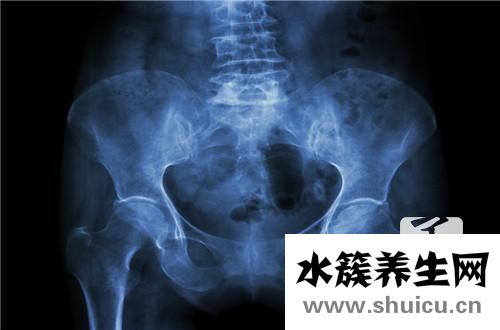

盆腔積液是一種常見的身心健康問題。如果盆腔積液超過10Mm,則屬于生理盆腔積液。這種盆腔積液對(duì)女性的身心健康是有害的,也會(huì)在疾病發(fā)生時(shí)給女性造成各種痛苦。比如肚子很疼,很可能是生理性的盆腔積液。下面我們來介紹一下盆腔積液!

盆腔積液便是骨盆存有炎癥性滲出液,可產(chǎn)生在子宮壁炎癥后,子宮內(nèi)膜組織發(fā)脹的體細(xì)胞中外滲的略粘稠的液體,被周邊組織包囊所逐漸產(chǎn)生的囊性包塊。如果不多方面醫(yī)治得話,能夠慢慢長(zhǎng)大。中藥材外治法可使藥力直通疾病,足以迅速充分發(fā)揮功效,快速改進(jìn)傷處生理作用,修補(bǔ)發(fā)炎組織。御雪清治療盆腔炎、盆腔積液以其安全性無副作用,故醫(yī)治盆腔炎癥中醫(yī)學(xué)是最好的選擇。除開女士因生理特征有一切正常的盆腔積液外,生理性的盆腔積液多是盆腔炎或孑宮內(nèi)膜異位癥。盆腔積液可產(chǎn)生在盆腔炎、附件炎或孑宮內(nèi)膜異位癥以后。按病理學(xué)要素可分成生理性盆腔積液和生理性盆腔積液二種。生理性盆腔積液對(duì)女士而言并不是是一件壞事兒,生理性盆腔積液傷害很大,一旦女士出現(xiàn)異常盆腔積液,應(yīng)立即到醫(yī)院門診就醫(yī),用藥治療。